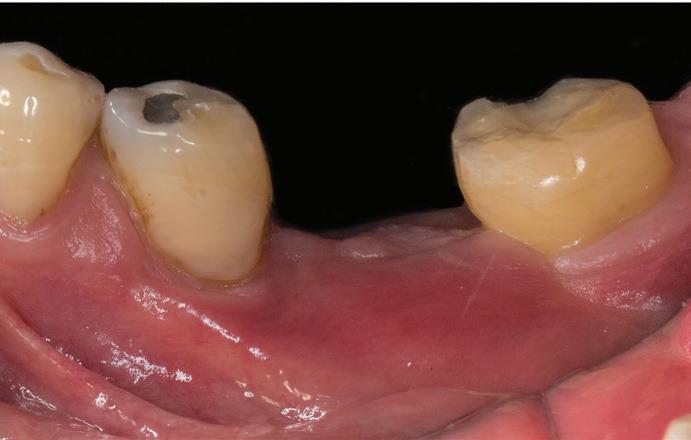

Chu44 35 M Swelling on left side of cheek FP,

Ferreira et al45 19 F Moderate headache, nausea, vomiting, left facial hypesthesia, low visual acuity FP, PP

Sohal et al46 24 M Massive swelling in right side of face FP

Linaburg et al47 50 F Massive swelling in left side of face Acanthomatous, FP

Abbreviations: F, female; FP, follicular pattern; M, male; NR, not reported; PP, plexiform pattern.